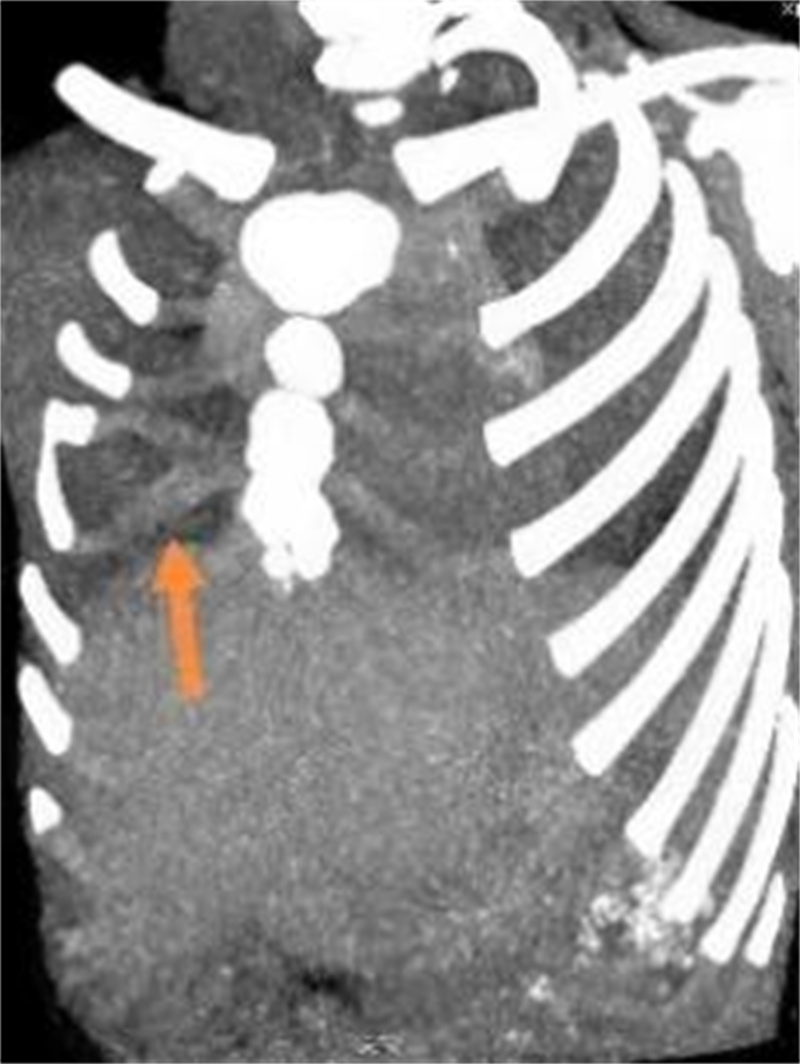

由于肋软骨在X线胸片上不显影,对于肋骨畸形的评价与确诊有局限性,目前多采用胸部 CT加肋骨重建检查。

可以,目前采用悬吊腔镜叉状肋切除术。叉状肋大部分分叉的上部肋软骨发育较细,且生长方向与其他正常肋骨走行角度不一致,这是导致胸壁凸起的原因之一。手术时,通常需切除分叉的上部软骨及分叉的部分硬骨。